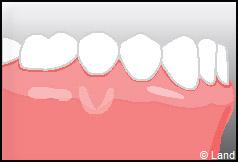

Les conséquences de cette mise à nu de la racine dentaire sont multiples, le patient peut présenter une hypersensibilité dentaire et l’aspect de ces récessions peut être inesthétique. Dans ce cas, la chirurgie muco-gingivale est recommandée et elle peut se faire de différentes façons.

Elles font appel à des lambeaux de gencive restante à proximité des récessions, qui sont déplacés et repositionnés sur la récession.

Elles font appel à un prélèvement sur le patient à un endroit où elle est en excès, qui est ensuite posé sur la récession.